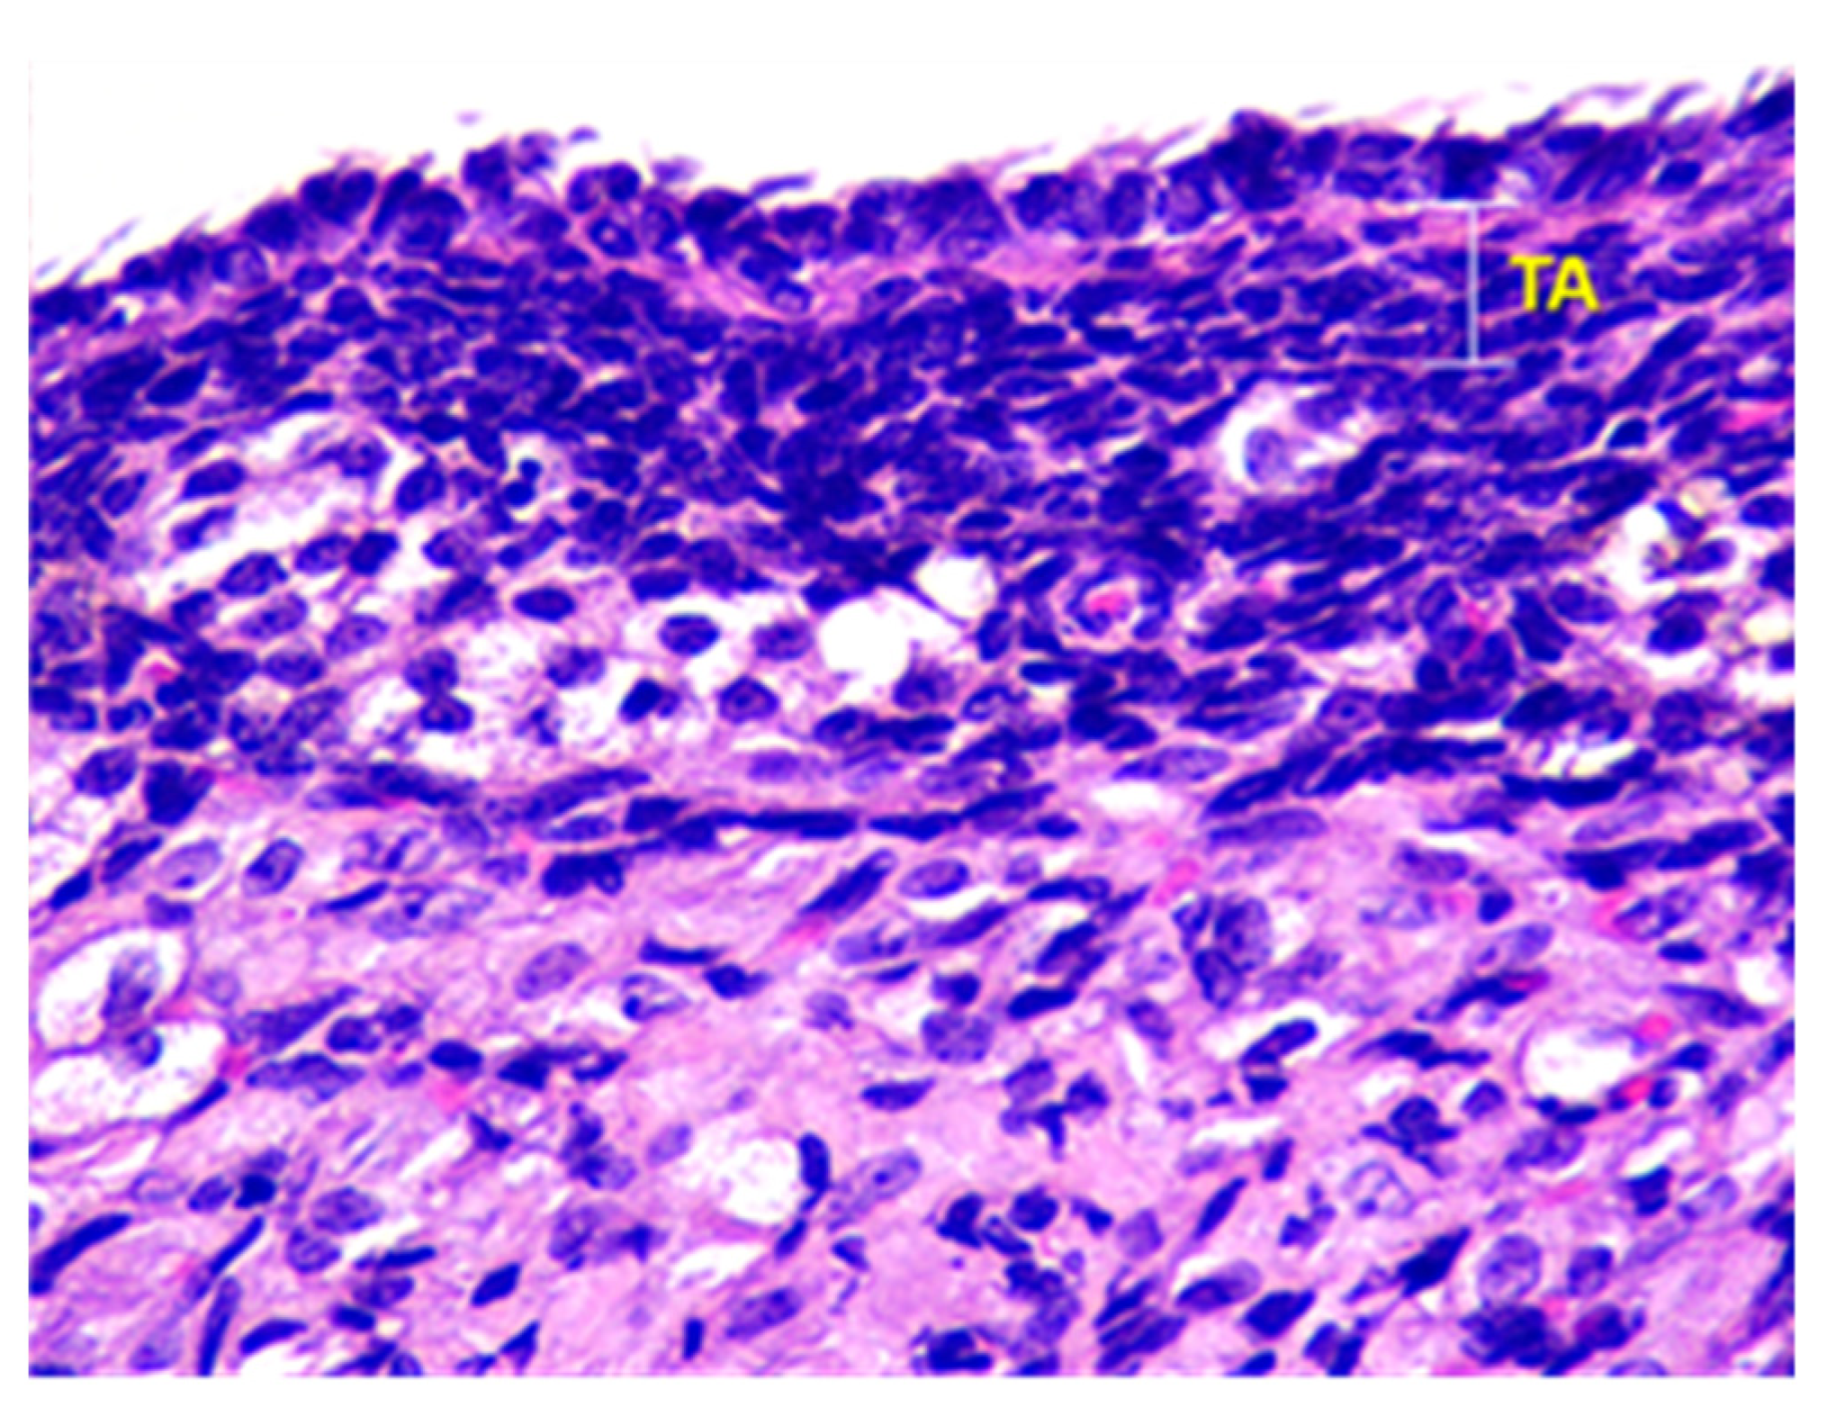

- Denefil, O.V.; Bilyk, Y.O.; Chorniy, S.V.; Fedoniuk, L.Y.; Chornii, N.V. The peculiarities of morpological changes of rats’ ovary and biochemical state under the damage with different doses of lead acetate. Wiad Lek. 2022, 75, 377–382. [Google Scholar] [CrossRef] [PubMed]